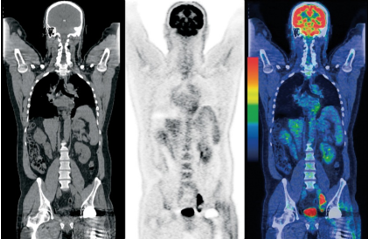

正電子斷層掃描利用放射性追踪劑 (Radioactive Tracer),用掃描儀器記錄人體影像。放射性追踪劑主要集中在組織中代謝活動較高的組織 (例如癌病組織),電腦按照放射性追踪劑發出輻射劑量。正電子斷層掃描通常結合電腦斷層掃描使用 (PET-CT scan),製成各部位的三維影像。

PET 掃描可以用作檢測和監控癌症,不單止檢測癌變組織的位置,也可以檢視癌變有否擴散至其他身體部位,協助癌症分期,亦可以檢測出早期癌變。